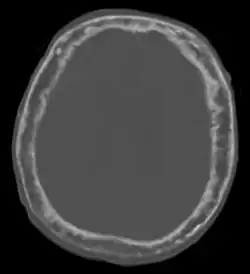

"This 92 year-old male patient presented for assessment of sudden inability to move half his body. An incidental finding was marked thickening of the calvarium. The diploic space is widened and there are ill-defined sclerotic and lucent areas throughout. The cortex is thickened and irregular. The findings probably correspond to the 'cotton wool spots' seen on plain films in the later stages of Paget's disease."